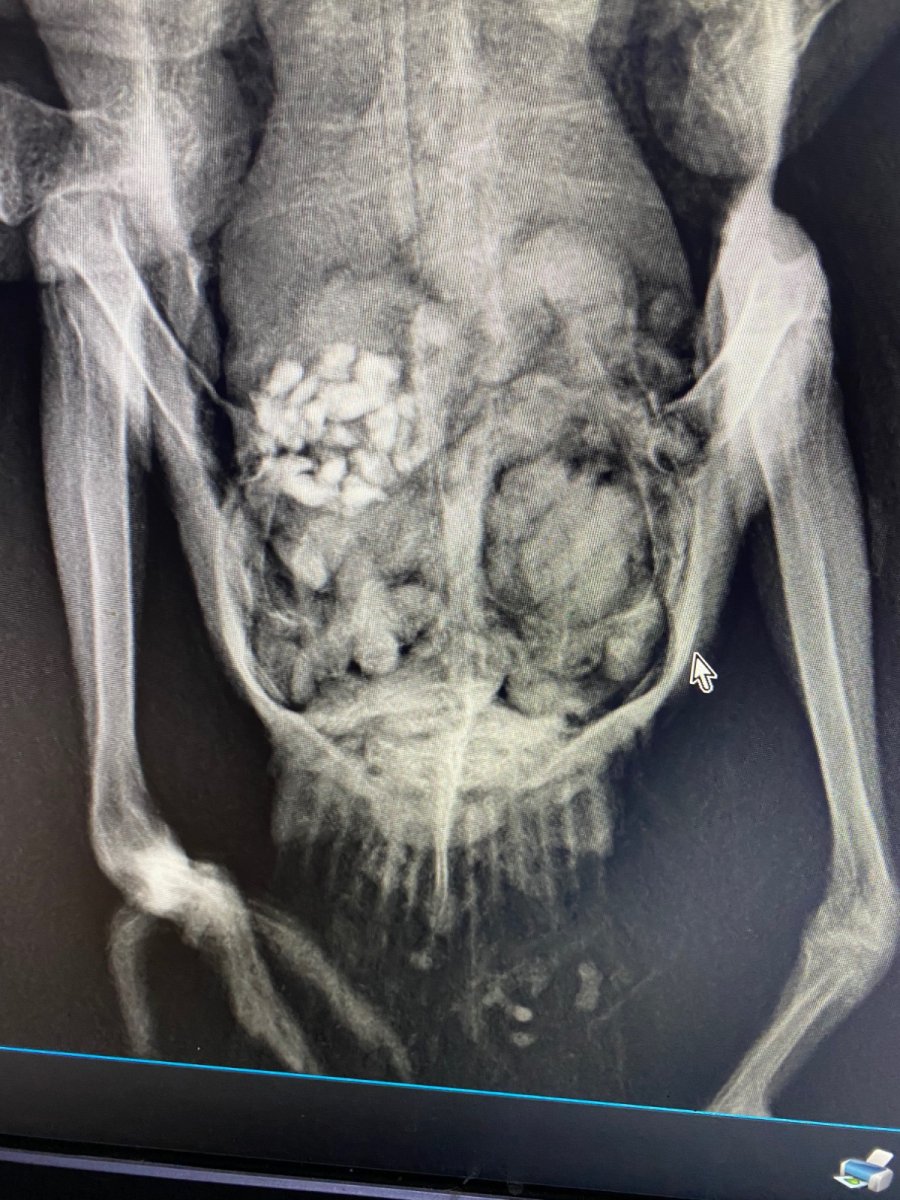

маленький принц Опубликовано 29 ноября, 2023 #126 Опубликовано 29 ноября, 2023 да у него пёрышки растут надо бы устроить купание налив в плошку чистой питьевой воды на сантиметр и затем поплескав в воде рукой чтобы он видел что там мелко и безопасно купание ОБЯЗАТЕЛЬНО под присмотром ВНИМАНИЕ сушить или греть феном птиц НЕЛЬЗЯ птицы очень легко травятся запахами горячего пластика потому что их лёгкие способны дышать разряжённым воздухом на огромной высоте В 17.10.2023 в 02:11, Анастасия Анатольевна сказал: а на лапках пока мы только так можем, попой кверху как сейчас ножки? В 29.09.2023 в 00:54, Анастасия Анатольевна сказал: @маленький принц здравствуйте! Извините пропала совсем( подходит к концу последняя неделя лечения Семен чувствует себя хорошо, на лапки не встаёт, сегодня сделали снимки ( он вырывался, поэтому держать пришлось вручную) сказали что все в норме с косточками и возможно это последствия на нервную систему какой-то инфекции и что ходить он не будет скорее всего 😭 удалось показать @Zosia рентген?